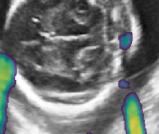

Fig. 6 compares the shadow confidence maps of the state-of-the-art methods and the proposed methods. RW and have the same parameters as used for Table I. The shadow confidence maps of the baseline, the proposed method and the proposedAG method are generated directly from input shadow images by confidence estimation networks. Overall, the proposed method and the proposedAG method achieve more visually reasonable shadow confidence estimation than the baseline and the state-of-the-art on different anatomical structures shown in Fig. 6. The proposed method and the proposedAG method are able to highlight multiple shadow regions while the RW algorithm shows limitations for most cases, especially for disjoint shadow regions.

Row I in Fig. 6 shows a fetal brain image from . The confidence estimation of shadow regions from the baseline, the proposed method and the proposedAG method are similarly accurate since we use fetal brain images to train the confidence estimation networks in these three methods. These outperform [16] and [22]. Rows (II-IV) in Fig. 6 show shadow confidence maps of non-brain anatomy from , including lips, abdominal and cardiac. The baseline failed on unseen data during inference. However, the proposed methods are able to generate accurate shadow confidence maps because of the generalized shadow features obtained by the shadow-seg module. Furthermore, the “Lips” example shows that our method is capable of detecting weaker shadow regions that have not been annotated in manual segmentation. This indicates that the confidence estimation network has learned general properties of shadow regions.